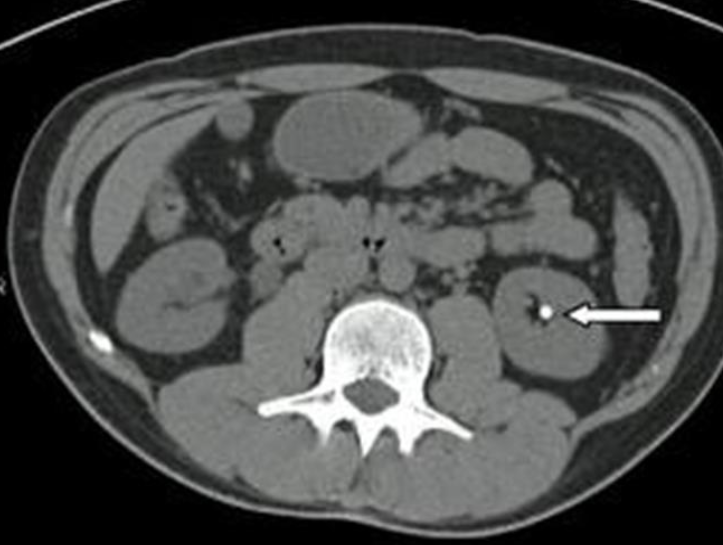

A. Give the name of the imaging examination in the given image. CT without contrast

B. Identify the abnormality marked by arrow in the given image? Kidney stone

US- There is a round, hyperechoic lesion at the upper pole of the kidney in the renal parenchyma, which shows a dorsal acoustic shadow and is most likely a kidney stone.

Hyperdense calculi located in the proximal third of the left ureter. As a result, the proximal ureter and the renal pelvis are dilated.